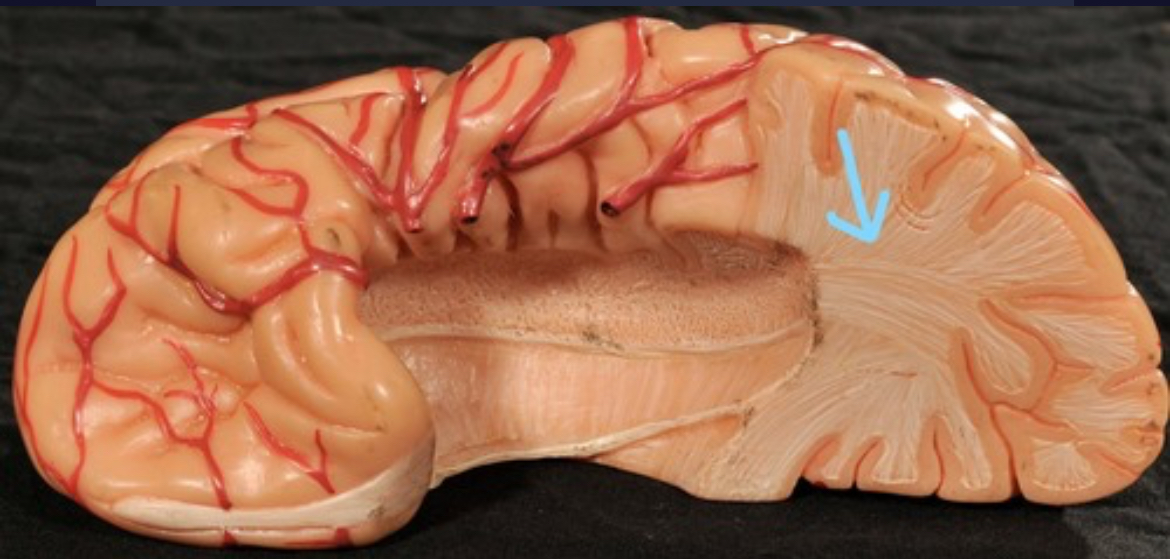

Cerebral cortex (gray matter)

Cerebral medulla (white matter)

Corpus callosum